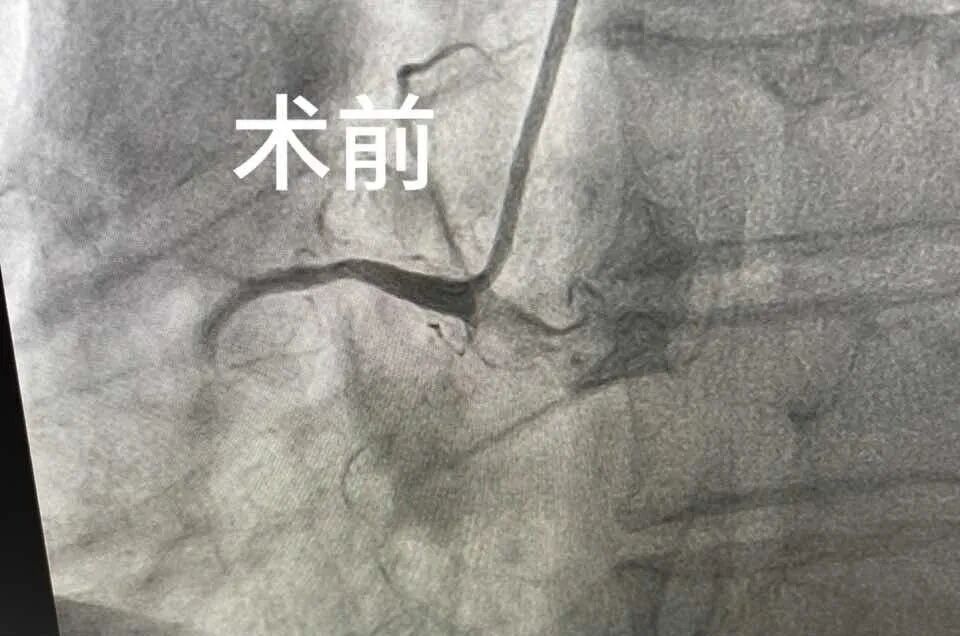

在海宁市中医院急诊科,张大伯嘴唇发白、意识模糊,生命体征不稳定。医护人员紧急为其开通绿色通道,发现心电图波形“不对劲”,提示为急性下壁心肌梗死。

“情况危急,立刻启动胸痛流程!”急诊科通过“医警联动”联系上了患者家属,充分沟通后,为张大伯进行了冠状动脉介入手术。及时的救治,使他转危为安,之后在心血管内科住院治疗,现已能下床行走。